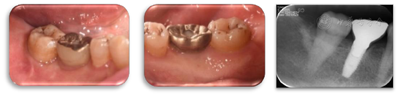

47叩痛(-),不松动,远中及颊侧中央PD7~9 mm,余位点PD3~4 mm,BI2-3,颊侧中央牙龈退缩约2 mm,无附着龈,舌侧牙龈无明显异常(图6,图7)。正中合未及早接触,侧方合未及合干扰,cbct示47颊侧及远中牙槽骨吸收超过根长2/3,颊侧骨缺损深约9 mm,宽约4 mm,远中骨缺损深约10 mm,宽约7 mm(图8,图9)